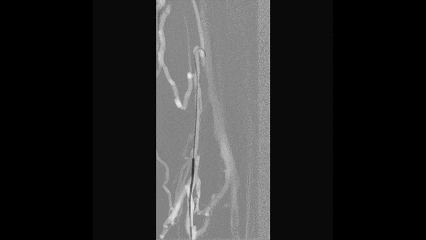

3

导丝通过技术

在路图模式下,使用泥鳅导丝通过股浅静脉侧支进入股深静脉

多次尝试后导丝通过闭塞的髂静脉段

交换0.035支撑导管配合导丝通过髂静脉闭塞段到达下腔静脉

4

轨道建立

由于6F长鞘无法从腘静脉推送至髂静脉段

穿刺右侧股静脉,建立从右股静脉到左腘静脉的轨道

将导管推送至左侧髂外静脉,交换cco导丝